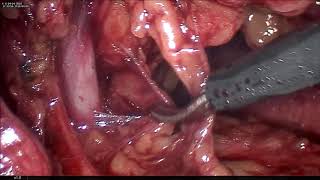

Nephrectomie coelioscopie video

Nephrectomie coelioscopie

Nephrectomie coelioscopie